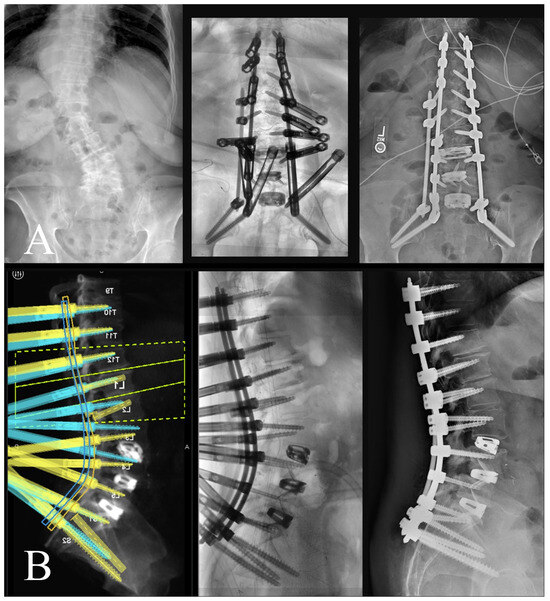

An intraoperative CT scan with a navigation frame attached to the patient is then obtained as a confirmation scan and to allow for navigated repositioning of any screws that are needed. A navigated burr is then used through the existing transfascial or percutaneous incisions to decorticate and drill out all facet joint levels that do not have anterior interbody fusions. These decorticated pockets are then packed with the bone graft of choice for the surgery. If needed, a mini-open exposure is performed for posterior column osteotomies (PCOs) to allow for further lordosis or scoliosis curve correction. Rods are then passed using a minimally invasive technique with rod passage inserters. While this historically has carried the possibility of great difficulty, the enabling technologies of planar screw planning has allowed this to proceed in very routine fashion. Satellite rods are first secured and locked into position so that their minimally invasive towers can be removed from the working airspace over the wound and any distractive techniques are completed if they are functional kickstand rods [16]. Placement of both main rods then follows. Acceptable alignment is then confirmed using a long film or a series of stitched X-rays (Figure 7). Closure proceeds in the usual fashion after all set screws are secured and towers removed.

This is an important adjunct to patient selection and operative planning, as the inclusion of these tools may increase the pool of patients in which MIS deformity correction may be considered. More recent reports have shown that in cases of even marked deformity, MIS techniques have shown to be quite effective while still benefiting from reduced complication profiles [23]. While these data may indicate that MIS approaches are feasible to correct ASD, they may not underscore the intraoperative limitations and challenges of applying such an approach. Anticipation of the challenges to applying MIS in ASD correction, such as tower collision, fixation of satellite rods, subfascial passage of rods, etc., is imperative for bringing these techniques into regular practice. Our report therefore advocates for preoperative planning of MIS constructs using robotic software to design these constructs in three-dimensional space, but also to modify screw and rod trajectories as intraoperative collisions and conflicts are anticipated. For example, Figure 7 illustrates a case in which two right-sided pedicle screws are preoperatively selected to affix to a satellite rod, rather than the main rod, with pre-adjusted trajectories of these screws allowing for easy intraoperative passage of right-sided rods. Loading pre-planned screw trajectories into the surgical robot ensures accurate and streamlined transfascial placement, accounting for previous components of the case during Stage 1 when interbody cages are placed. Also illustrated in Figure 7 is the omission of a of the left L5 pedicle screw, to avoid tower collision when lordosis correction is achieved. Tower collision at the lumbosacral junction is a common spatial limitation in the operative workspace and may be difficult to anticipate as lordosis correction is achieved during open surgery. This demonstrates how preoperative planning software may aid in anticipating intraoperative spatial limitations of the workflow and permits adjustments of the construct design to yield a surgical plan which achieves an optimal surgical correction but is also technically feasible through an MIS approach. Prior studies showing use of robotics in adult spinal deformity have mostly relied on accuracy of screws or placement of S2-alar-iliac pelvic fixation, which highlights the need to expand upon the benefits of robotics use specifically during this planning stage [24].

Figure 7. (A) (left) Preoperative AP X-ray; (middle) intraoperative AP long film showing appropriate coronal correction; (right) postoperative standing AP X-ray. (B) (left) Preoperative robotic plan with patient-specific rod geometry; (middle) intraoperative sagittal long film with appropriate sagittal correction; (right) postoperative standing lateral X-ray.